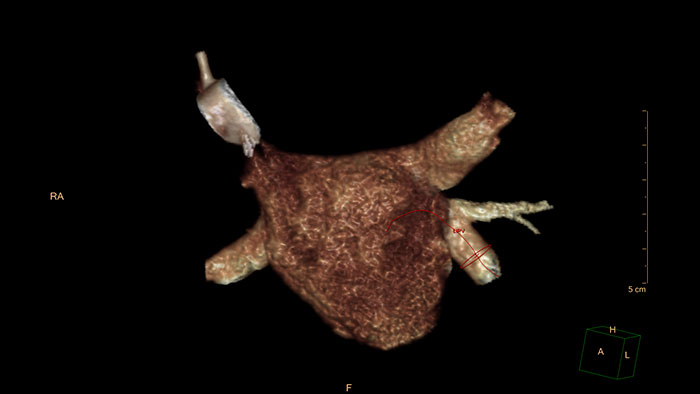

Myocardial Defect Assessment

CT Myocardial Defect Assessment

Assessing myocardial defects

Relies on the automatic 3D model-based whole-heart segmentation from the CCA application to provide visual and quantitative assessment of segmented, low-attenuation areas within the left ventricle myocardium from a single, gated cardiac CTA scan.

Benefits

• Volumetric visualization of coronary arteries along with segmentation maps can be displayed as an overlay on top of a 3D myocardial surface.

• Quantitative information includes volume of low attenuation areas within the myocardium and their percentage out of the total myocardial volume.